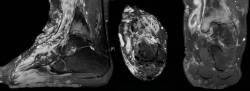

Una paciente de 30 años de edad, previamente diagnosticada con síndrome de Klippel-Trénaunay, presentaba antecedentes de dolor crónico del tobillo derecho y hemorragias intraarticulares recurrentes. En el examen, se observó dolor y limitación del rango de movimiento pasivo y activo de la articulación tibiotalar. Las varices estaban presentes en la parte delantera y media del pie, así como en la parte anterior de la articulación del tobillo (Figura 1), impidiendo la realización de cualquier abordaje, ya fuera abierto o artroscópico en la parte anterior, medial y lateral del tobillo. Solo se respetaba un área que se extiende desde ambos lados del tendón de Aquiles hasta el lado posterior de ambos maléolos (Figura 2). Las radiografías simples mostraron una buena alineación de la articulación y la resonancia magnética nuclear (RMN), signos degenerativos del cartílago del astrágalo y la tibia distal, aparte de constatar la presencia masiva de malformaciones arteriovenosas (Figura 3).

Figura 1. Vistas plantar, medial y dorsal que muestran la afectación del pie y el tobillo por las fístulas arteriovenosas que impide la realización de abordajes quirúrgicos por estas vías, incluso artroscópicos.

Figura 2. Vistas posterolateral (arriba) y posteromedial (abajo), que muestran la zona segura para realizar los portales en los que no existe afectación por la enfermedad.

Figura 3. De izquierda a derecha: corte sagital, axial y coronal de resonancia magnética nuclear que muestra la afectación de partes blandas y la presencia de signos degenerativos en la articulación tibioastragalina.